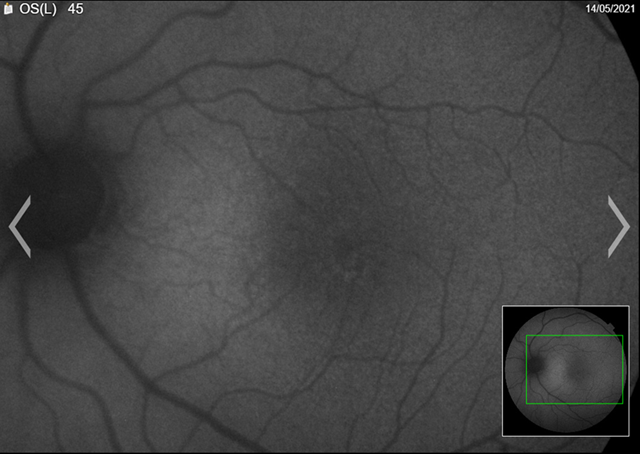

Fundus

autofluorescence (faf) is a non-invasive imaging modality that captures an

image from ocular endogenous fluorophores found within the retinal pigment

epithelium and the choroid. These are composed mainly of lipofuscin and

melanin. By capturing an image composed

of the distribution of lipofuscin and melanin, the clinician can formulate an

impression of the health of the retina/rpe.

The patient’s faf was abnormal. We could see from the images that there were areas of hyper and hypo-autofluorescent spots circumferentially, with the left more defined than right (figures 4a,4b). Magnified images showing defects more clearly (figures 5a,5b).

(a) Right eye

(a)

Left eye

figure 4. Fundus autofluorescence (faf)

(a) Left eye

Figure 5. Fundus autofluorescence (faf) (magnified)